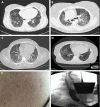

Scleroderma-related interstitial lung disease (SSc-ILD) is a pulmonary fibrosing disorder characterized by systemic inflammation and progressive scarring of the lungs that leads to respiratory failure. Although certain immunosuppressive therapies may slow disease progression, current treatment strategies are not curative; consequently, SSc-ILD continues to be a major cause of morbidity and mortality. We present four cases of SSc-ILD that emphasize the importance of early screening and detection, close follow-up, and aggressive management. We also highlight the need for well-conducted clinical trials designed to identify new and effective treatments.